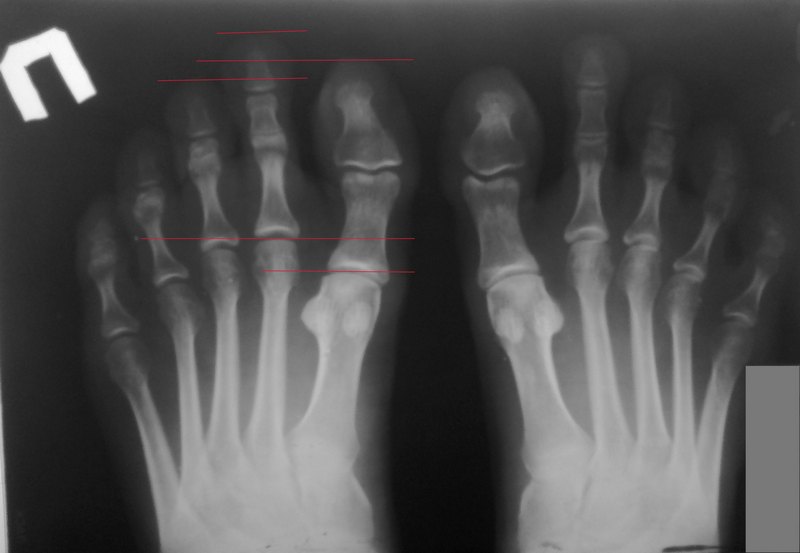

Девушка 28 л. обратилась с жалобами на косметический дефект обеих стоп - выстояние 2-х пальцев из общего ряда. Выполнена Р-графия (см. в приложении) - по моему мнению имеет место укорочение 1-х плюсневых костей. Кроме косметического дефекта других жалоб со стороны стоп не предъявляет. За счет того, что размер обуви подбирается по 1-м пальцам, второй палец постоянно подогнут и формируется его молоткообразная деформация. Как можно помочь?

Напрашивается логичный вариант удлинения 1-х плюсневых костей, но от него пациентка категорически отказывается (увеличится размер обуви :) ). Может что-то предпринять со 2-ми пальцами: резекция оснований основных фаланг (но в таком возрасте очень не хочется), либо же укорачивающая остеотомия основных фаланг...